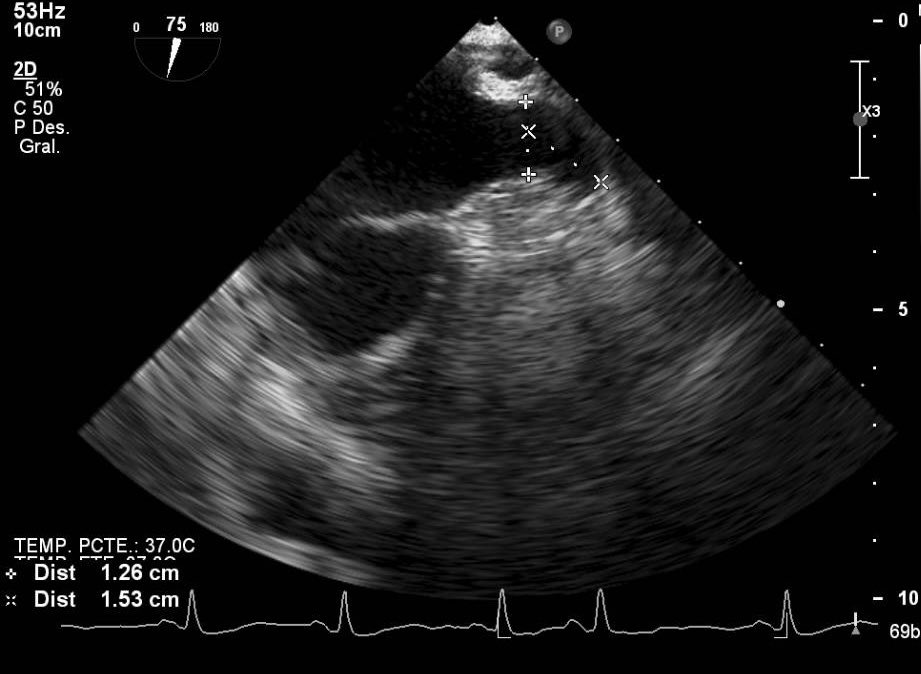

La versatilidad del dispositivo Watchman FLX permite cerrar orejuelas complejas como esta. Su pequeño tamaño supuso un reto pero finalmente conseguimos ocluirla con éxito. @GVAdsTorrevieja @CenturyRaul @bostonsci

0

11

19